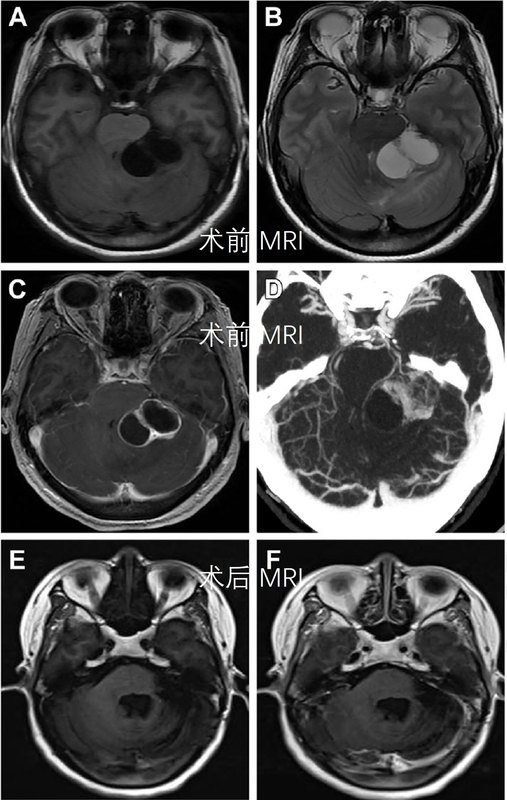

神經(jīng)系統(tǒng)有一種腫瘤,叫“血管母細(xì)胞瘤”。一說“母細(xì)胞瘤”,很多人認(rèn)為這應(yīng)該是個(gè)惡性腫瘤。恰恰相反,“血管母細(xì)胞瘤”是由腦神經(jīng)和脊髓神經(jīng)所產(chǎn)生的一種高度血管分化的良性腫瘤,占顱內(nèi)腫瘤的0.8~1.9%,多發(fā)生于小腦,也見于第四腦室、腦干、脊髓和大腦等處。該病以青壯年為主,好發(fā)于20-40歲,男性多于女性。有固體狀和囊泡狀兩種基本形態(tài)。世界衛(wèi)生組織(WHO)將其分類為起源未明的I級(jí)腫瘤,分為散發(fā)性和家族遺傳性兩種。大多數(shù)的血管母細(xì)胞瘤由單一病灶所產(chǎn)生,也可是一種罕見的家族性腫瘤綜合征“Von Hippel-Lindau綜合征”的表現(xiàn)之一。由于該病早期常無癥狀或輕微癥狀,如頭痛等,發(fā)現(xiàn)時(shí)往往病灶較大。位于小腦血管母細(xì)胞瘤常表現(xiàn)為頭痛、惡心、嘔吐、步態(tài)不穩(wěn)等;腦干血管母細(xì)胞瘤表現(xiàn)為感覺遲鈍、站立不穩(wěn)、步態(tài)改變、眼球震顫、構(gòu)音障礙、吞咽困難、頭痛、反射亢進(jìn)、食欲減退等;脊髓血管母細(xì)胞瘤表現(xiàn)為肢體感覺減退、肢體麻木、放射性疼痛、乏力、站立不穩(wěn)等。在一些少見的病例中,這種腫瘤會(huì)由于一些和神經(jīng)學(xué)不相關(guān)的癥狀或是疾病,而無意中被發(fā)現(xiàn)。分享兩例我院血管母細(xì)胞瘤手術(shù)病例,如下:患者,男,45歲,因“右上肢麻木半年”入院,查體未見明顯陽(yáng)性神經(jīng)系統(tǒng)體征。磁共振檢查提示四腦室內(nèi)延髓背側(cè)囊性占位,腫瘤右后方可見很小一部分囊壁強(qiáng)化(不仔細(xì)看就遺漏了,該強(qiáng)化是血管影也有可能)。術(shù)前診斷考慮四腦室內(nèi)蛛網(wǎng)膜囊腫?血管母細(xì)胞瘤?術(shù)中見分曉。 磁共振提示延髓背側(cè)囊性占位,T1低信號(hào),T2高信號(hào)DWI像呈低信號(hào),增強(qiáng)不明顯,腫瘤囊壁右后側(cè)很小一部分強(qiáng)化影(血管強(qiáng)化不除外)術(shù)中可見腫瘤呈囊性,囊壁右后方可見小結(jié)節(jié)(與術(shù)前磁共振強(qiáng)化影相對(duì)應(yīng))。術(shù)后CT提示腫瘤切除,未見明顯出血患者于全麻下頸后正中入路行延髓腫瘤切除術(shù)。暴露小腦扁桃體和延髓后,腫瘤位于四腦室內(nèi),與延髓黏連,呈灰白色囊性,切除部分囊壁后可見0.5*0.6cm大小灰紅色瘤結(jié)節(jié),瘤結(jié)節(jié)予以完全切除,囊壁部分切除。手術(shù)過程順利,術(shù)后患者恢復(fù)良好,右手麻木好轉(zhuǎn),無新發(fā)神經(jīng)系統(tǒng)陽(yáng)性體征?;颊?,女,37歲,因“右上肢麻木3月”入院。查體未見明顯陽(yáng)性神經(jīng)系統(tǒng)體征。磁共振檢查提示延髓背側(cè)占位,伴臨近延髓部分水腫,可見部分強(qiáng)化。術(shù)前診斷考慮延髓背側(cè)占位,血管母細(xì)胞瘤可能。磁共振提示延髓背側(cè)囊性占位,T1低信號(hào),T2高信號(hào)增強(qiáng)可見部分強(qiáng)化影術(shù)后CT提示腫瘤切除,未見明顯出血術(shù)后病理:血管母細(xì)胞瘤?;颊哂谌橄骂i后正中入路行延髓腫瘤切除術(shù)。術(shù)中見腫瘤位于延髓背側(cè),呈淡黃色囊性,切除部分囊壁后可見灰紅色瘤結(jié)節(jié),瘤結(jié)節(jié)予以完全切除,囊壁部分切除。手術(shù)過程順利,術(shù)后患者恢復(fù)良好,右手麻木好轉(zhuǎn),無新發(fā)神經(jīng)系統(tǒng)陽(yáng)性體征。如果年輕人出現(xiàn)了頭痛、手臂麻木、站立不穩(wěn)等癥狀,及時(shí)就醫(yī)是關(guān)鍵,切不可因“年輕”拖延,錯(cuò)過了最佳治療期。血管母細(xì)胞瘤因其良性的特性,手術(shù)治療是血管母細(xì)胞瘤的首選治療方法,腫瘤完全切除可達(dá)根治效果。